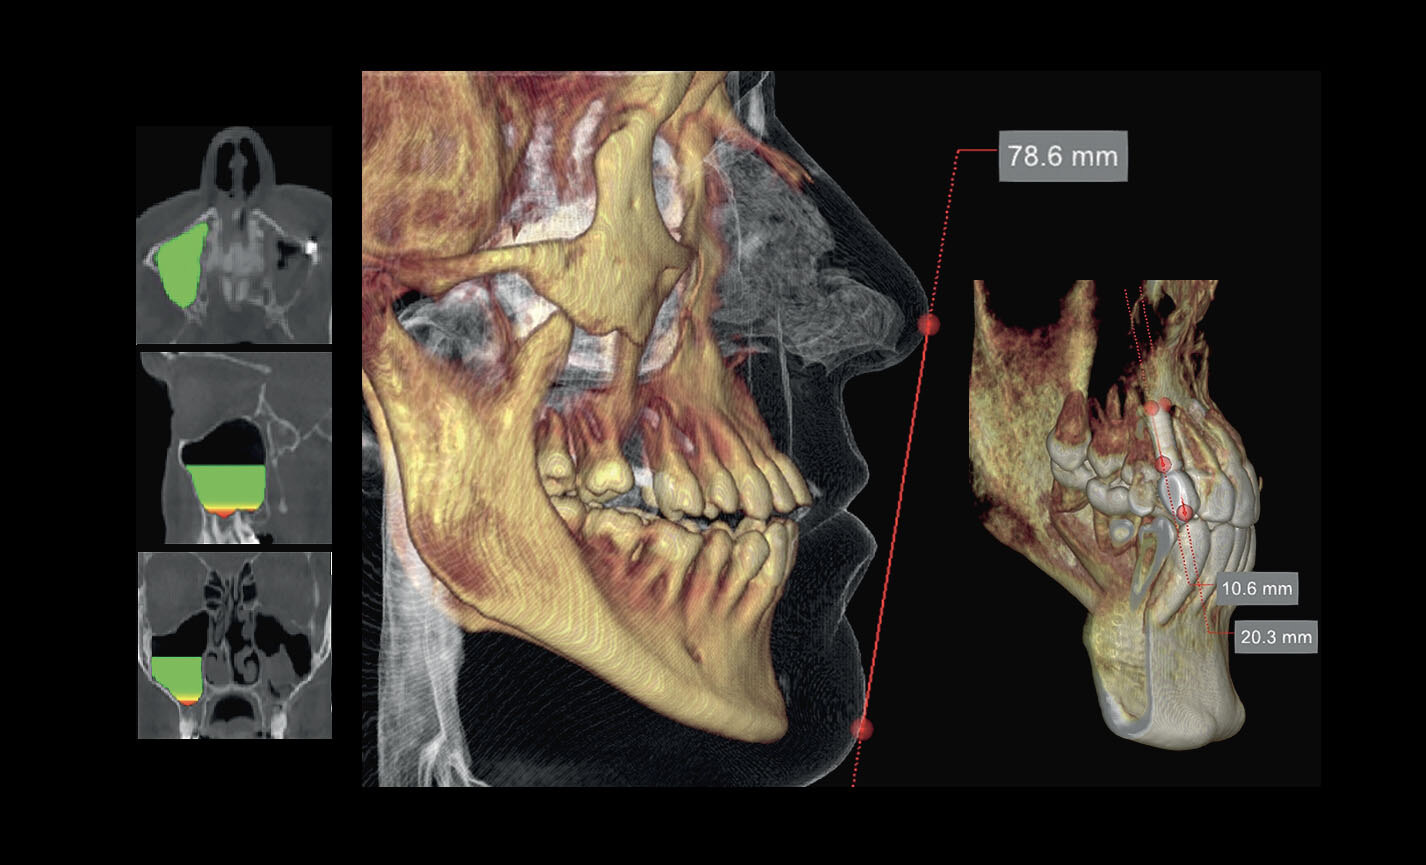

Analyses volumétriques

La fonction du logiciel de calcul du volume de soulèvement du sinus maxillaire permet de déterminer l’intervention à l’avance et d’opérer en toute sécurité. Il est en outre possible de tracer des lignes directement sur le modèle virtuel du patient en évaluant les rapports morphologiques sur le rendu 3D.

Évaluation des implants zygomatiques

Les volumes avec FOV 13 x 8 cm, ou 13 x 10 cm, représentent l’outil idéal pour la planification des implants zygomatiques. En effet, le diamètre de 13 cm est le seul qui permet d’inclure tout le zygoma dans le balayage, sans coupes.